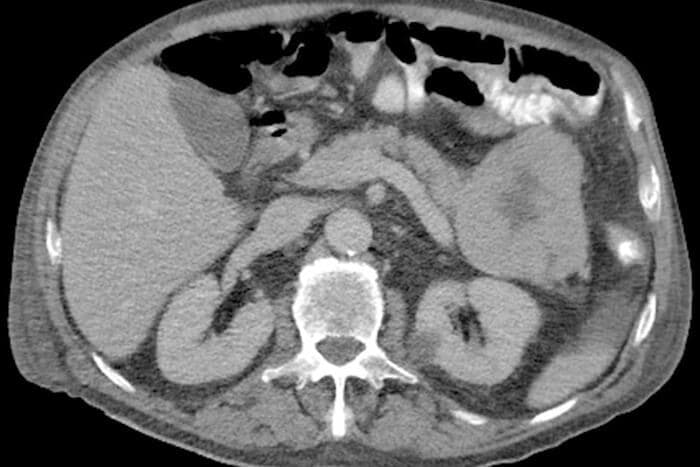

Dieses Azinuszellkarzinom im Bereich des Pankreasschwanzes stellt sich in der CT als zentral hypodense, regressiv veränderte Raumforderung mit relativ glattem Rand dar.